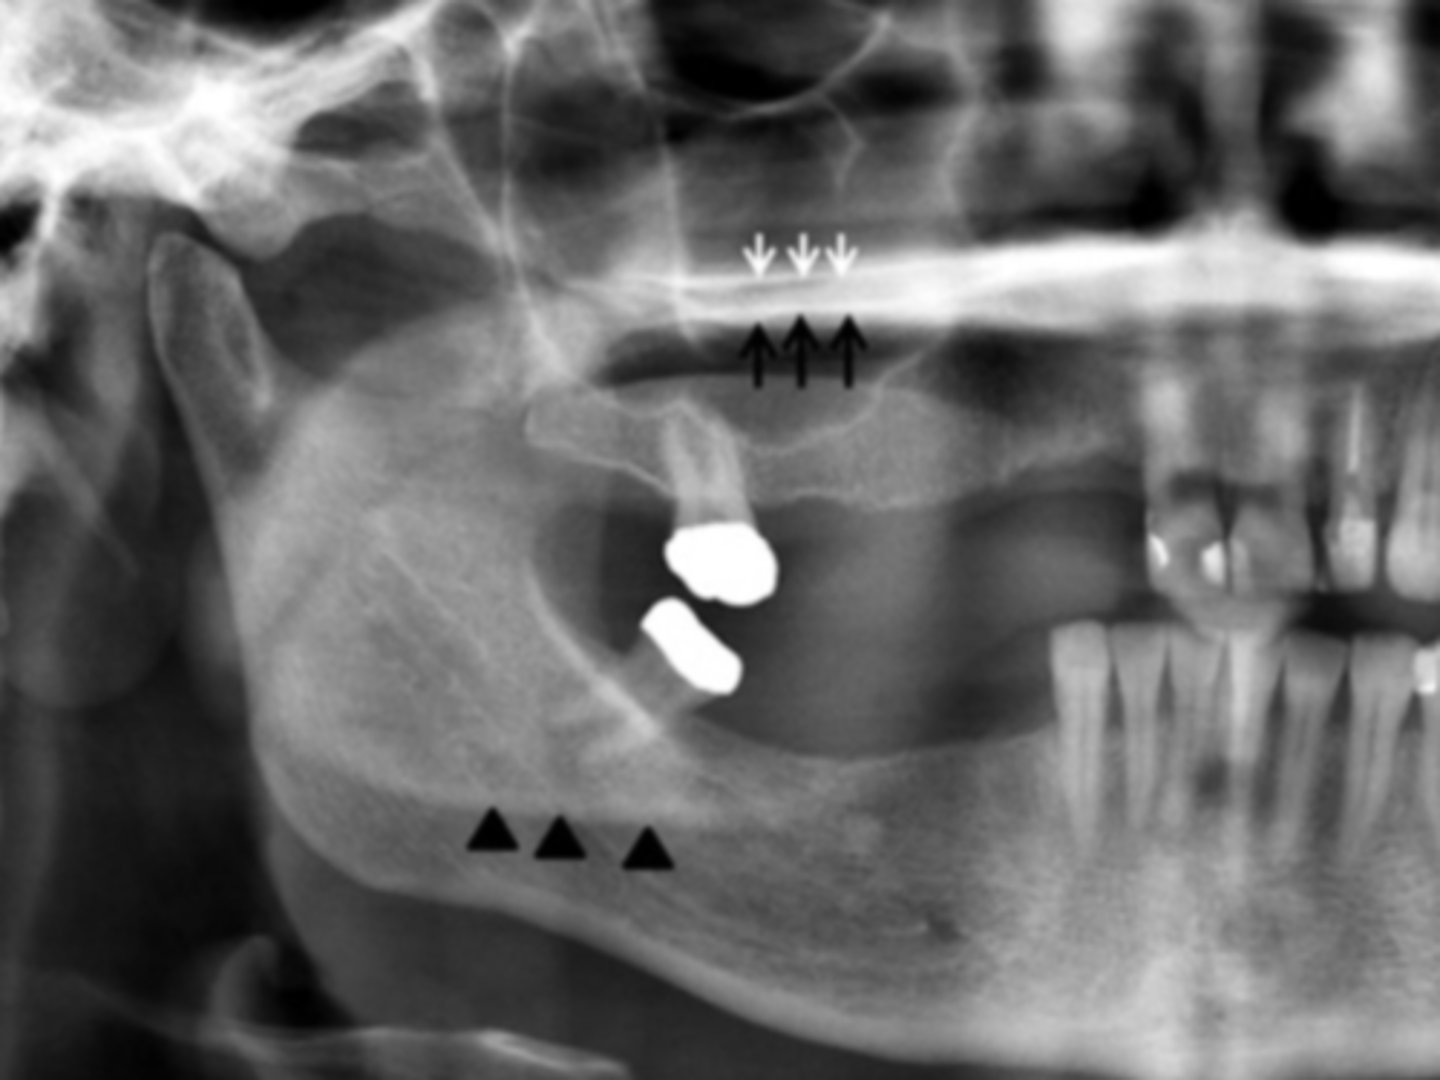

B) ghost

The white arrows represent the ___ hard palate

A) real

The black arrows represent the ___ hard palate

B) ghost left mandible

The black triangles represent the ___

A) real left mandible

C) real right mandible

D) ghost right mandible